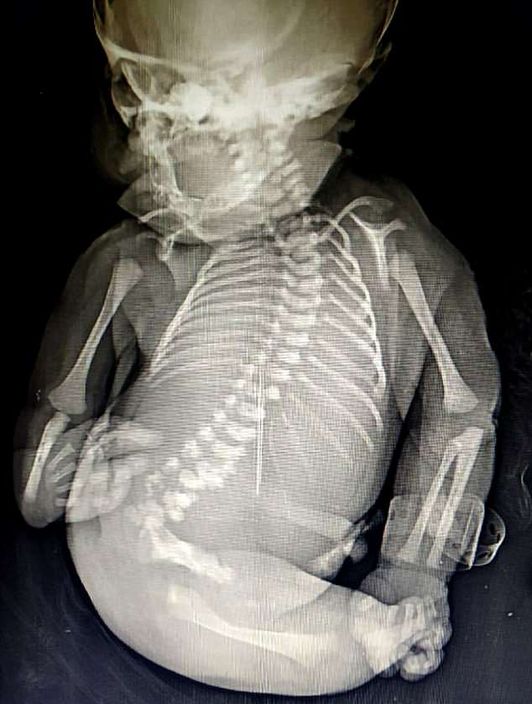

印度媽誕「美人魚」寶寶 雙腳相連僅活了15分鐘

由於Disksha在懷孕期間沒有積極產檢,只有在懷孕八個月時進行過一次超音波檢查,所以到出生時,才第一次看到寶寶的狀況。寶寶雙腳骨骼發育不全,而且連在一起,看起來就像是美人魚的魚尾,加上缺少了性器官,醫生無法判定性別,更令人傷心的是寶寶出生僅15分鐘便夭折。